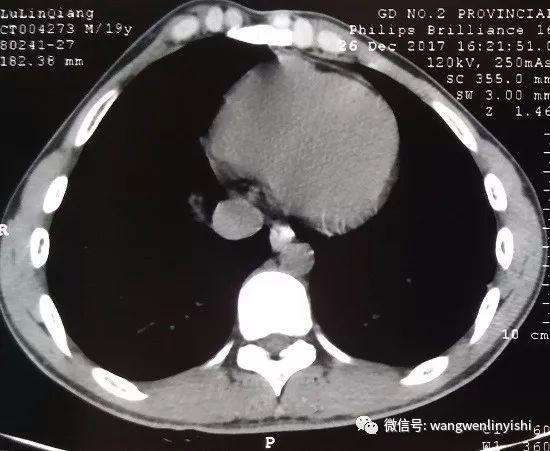

术前检查

胸壁存在大面积的严重凸起,凸起左右对称,主要位于胸壁的上半部分,下半部分胸壁的两侧还同时存在轻度凹陷。